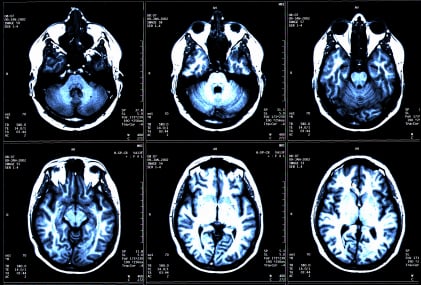

La sclerosi multipla è una malattia neurologica che causa la progressiva perdita del controllo muscolare. Ciò si verifica quando il sistema immunitario, per ragioni ancora da chiarire, produce anticorpi che distruggono la mielina, quella sostanza che isola le cellule nervose e che consente la corretta conduzione degli impulsi nervosi.

La conduzione dell’impulso nervoso di nervi mielinizzati è infatti circa 100 volte più veloce di quella di nervi non mielinizzati.